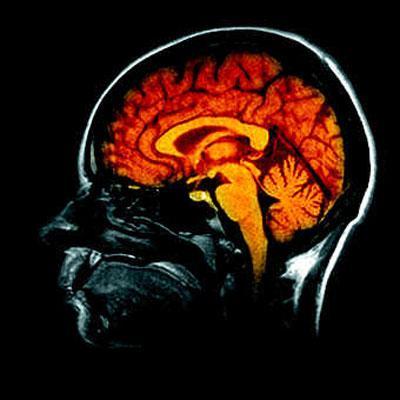

Pour résumer, en travaillant sur l’hippocampe de rats de laboratoire, la zone du cerveau qui est responsable de la mémorisation, les chercheurs ont réussi à manipuler les rongeurs via une prothèse cérébrale. Le système électronique permet de doubler les signaux dans la zone du cerveau associée à la mémoire. Lorsque le dispositif est testé sur des rats déficients, il permet de restaurer les fonctions cérébrales perdus. Mieux encore, lorsqu’il est utilisé sur des rats « normaux », l’appareil permet d’améliorer sensiblement leur capacité mémorielle !

Cet implant apporte donc la preuve que le code neuronal du cerveau peut être interprété et reproduit pour améliorer les fonctions cognitives. Non seulement l’activité cérébrale peut être lue, mais il est désormais possible de la manipuler…